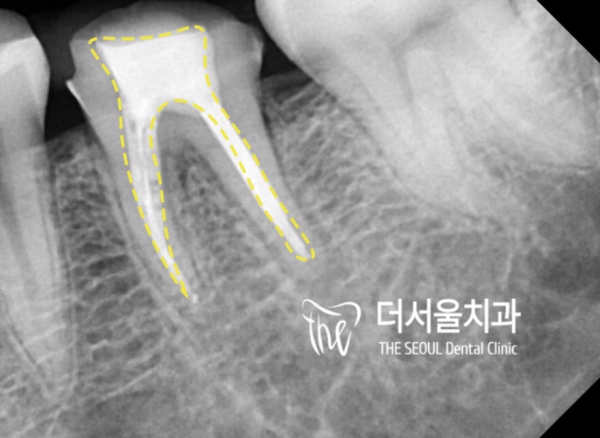

엑스레이를 통해 환자분의 치아 내부를 확인하니

치수강 근처까지 감염이 진행된것을 확인하였습니다.

이러한 경우에는 신경치료를 통해 이시림을 개선할 수 있습니다.

X-rays show the inside of your teeth

We confirmed that the infection has progressed to near the dental pulp.

In this case, neuropathy can be improved through neuropathy.